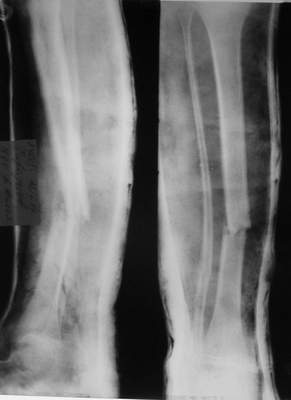

Ребенок 12 лет, поступил после падения с высоты примерно 2,5м.

Перелом костей н\3 правой голени со смещением. Перелом большеберцовой кости можно охарактеризовать как компрессионно-оскольчатый.

Скелетное вытяжение за пяточную кость.

В первые сутки значительный отек с\3, н\3голени, стопы с развитием практически неуловимого в нашей стране ;) компартмент синдрома (фасциотомии не проводилось), недочеты по укладке на скелетном

вытяжении.

Формирование некроза кожи по задней поверхности н\3 голени~ 1 %, вторичное заживление, кожная пластика. Нейропатия м\берцового нерва (отсутствие активного разгибания 1 пальца) На вытяжении около 8 нед, в дальнейшем в гипсовых повязках ~ 8 мес.

A> Перелом костей н\3 правой голени со смещением.

Это от 13.10.04? А это близкие к первичным снимки?

A> Перелом большеберцовой

A> кости можно охарактеризовать как компрессионно-оскольчатый.

Есть один осколок... Ма-аленький такой... Но из-за этого стоит ли весь

перелом характеризовать как оскольчатый?

Нормальный такой перелом... "шарнирный" я бы сказал... ну да есть

элемент сдавления (компрессии) по оси... и что?

Первичные

|

Вытяжение